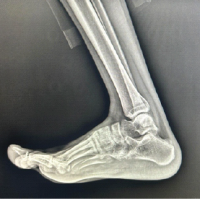

At 5 years post-operative, he continued to have no limitations to his activities, and he remained free of any pain or mechanical symptoms. In fact, he has become active in triathlons and competitive distance running. X-rays at this time showed completely healed fractures, intact hardware, and well-preserved joint spaces with continued mild genu valgum on the right (Fig. 6). Knee range of motion has remained full, and leg length and muscle bulk remain symmetrical bilaterally (Fig. 7).